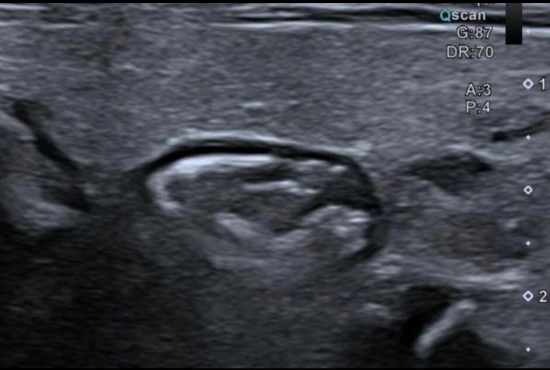

"Quand une douleur testiculaire cache une hernie inguinale : l'importance de l'exploration systématique des orifices herniaires"

25/04/2026